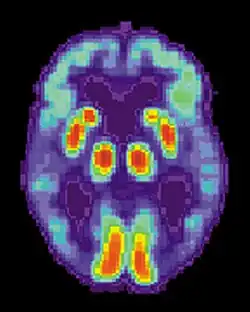

Figure 4. PET scan

Positron emission tomography (PET) figure 4

PET scans use nuclear imaging to trace the presence a particular radioactive glucose or sugar. Glucose is the main fuel of the brain (Harris et al., 2018). Essentially, the sugar is injected into the body via a vein in a very small amount, and the PET scanner is able to see which areas of the brain are using the glucose up. The scanner uses this information to create a 3D image of the area being scanned, in this case the brain. This change in metabolic process is what allows the researchers using the PET scanner to determine the most active areas of the brain. This is not always a preferred method due to the use of radioactive material. Even though it is small, researches may need to perform multiple scans, and radiation can build up over time (Harris et al., 2018).